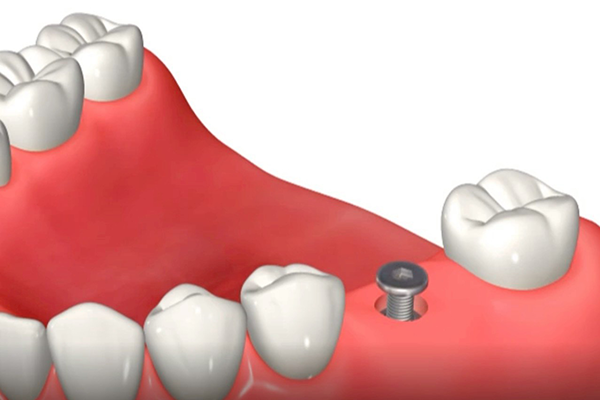

埋入直後のインプラント体と周囲骨との間の嵌合力により得られる機械的な固定を初期固定と言います。初期固定は、インプラント体の形状、骨質や骨量、手術術式、などに影響されます。一方、埋入後の骨治癒が進行してインプラント体が安定してくる生物学的固定を二次固定といいます。

この画像のように、埋入直後はインプラント体と骨の間は機械的な固定があるのみですが、段々と時間が経ち治癒が進行してくると、しっかりとした二次固定が得られるようになります。